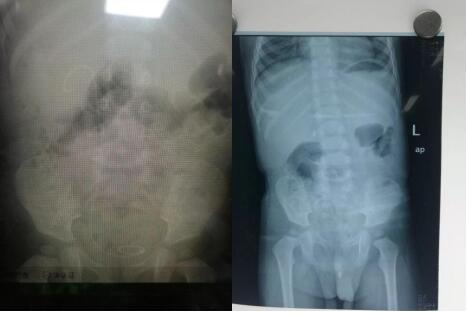

我院泌尿外科成功为一岁半患儿实施 尿道结石钬激光碎石术